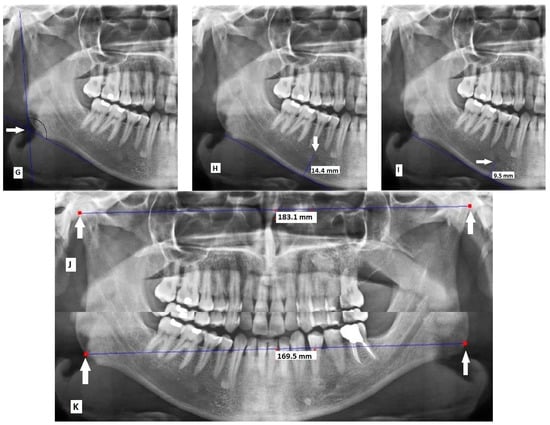

- Maximum ramus width: Maximum anteroposterior ramus width (Figure 1A) [16].

Figure 1. Measurements made on panoramic radiographs: (A) maximum ramus width; (B) minimum ramus width; (C) condylar height; (D) coronoid height; (E) antegonial angle; (F) antegonial depth; (G) gonial angle; (H) distance between the superior border of the mental foreman and the inferior border of the ramus; (I) distance between the inferior border of the mental foramen and the inferior border of the ramus; (J) bicondylar breadth; and (K) bigonial breadth. - Minimum ramus width: Minimum anteroposterior ramus width (Figure 1B) [16].

- Condylar height: Distance between the most superior part of the condyle and the most inferior part of the inferior border of the body of mandible (Figure 1C) [19].

- Coronoid height: Distance between the most superior part of the coronoid process and the most inferior part of the inferior border of the body of mandible (Figure 1D) [20].

- Antegonial angle: Intersection of two lines at the deepest point of the inferior border of mandible. The first line passes through the anterior part of the inferior border of mandible and the second line passes through the inferior border at the gonion (Figure 1E) [21].

- Antegonial depth: Vertical distance between the inferior border of the mandible and its deepest point (Figure 1F) [21].

- Gonial angle: Angle formed between the following two lines: A line tangent to the ramus and the mandibular condyle, and a line tangent to the most inferior part of the gonial section and the body of the mandible (Figure 1G) [18].

- Distance between the superior border of the mental foramen and the inferior border of the ramus (Figure 1H) [22].

- Distance between the inferior border of the mental foramen and the inferior border of the ramus (Figure 1I) [23].